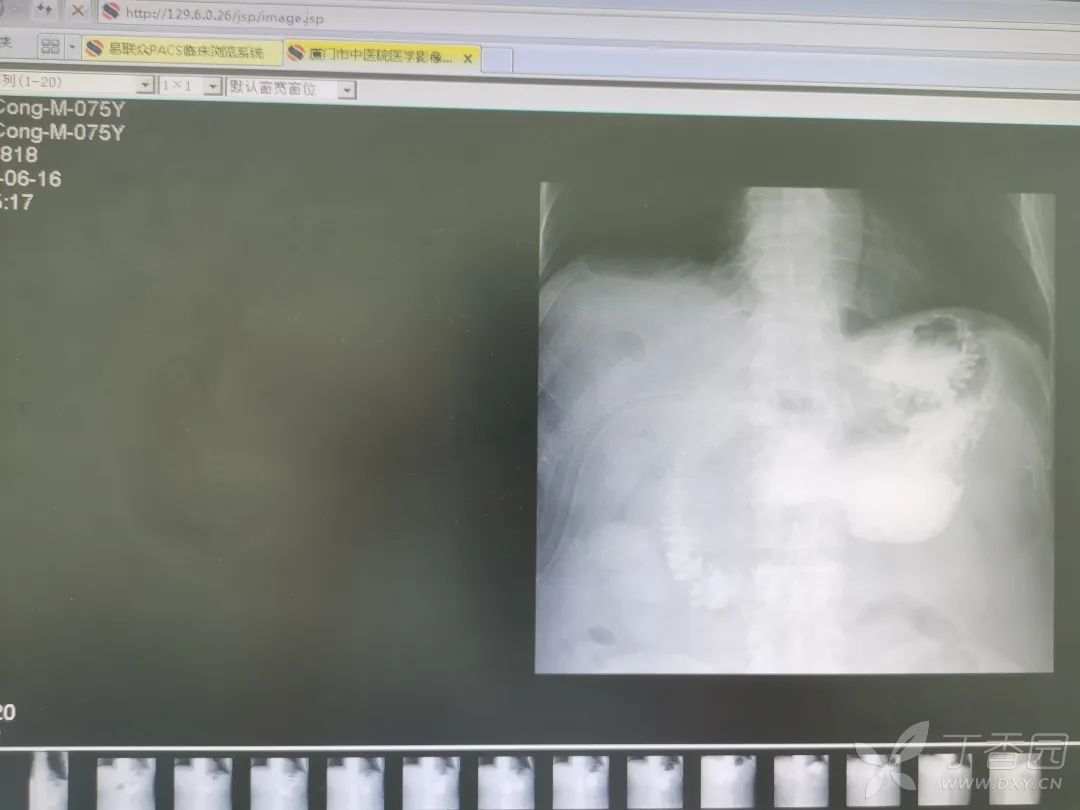

术后第 7 天口服碘剂行上消化道造影,未见明显造影剂外漏及肠梗阻征象,拔出空肠营养管,术后第 10 天拔除肝下引流管,办理出院。

术后造影图片